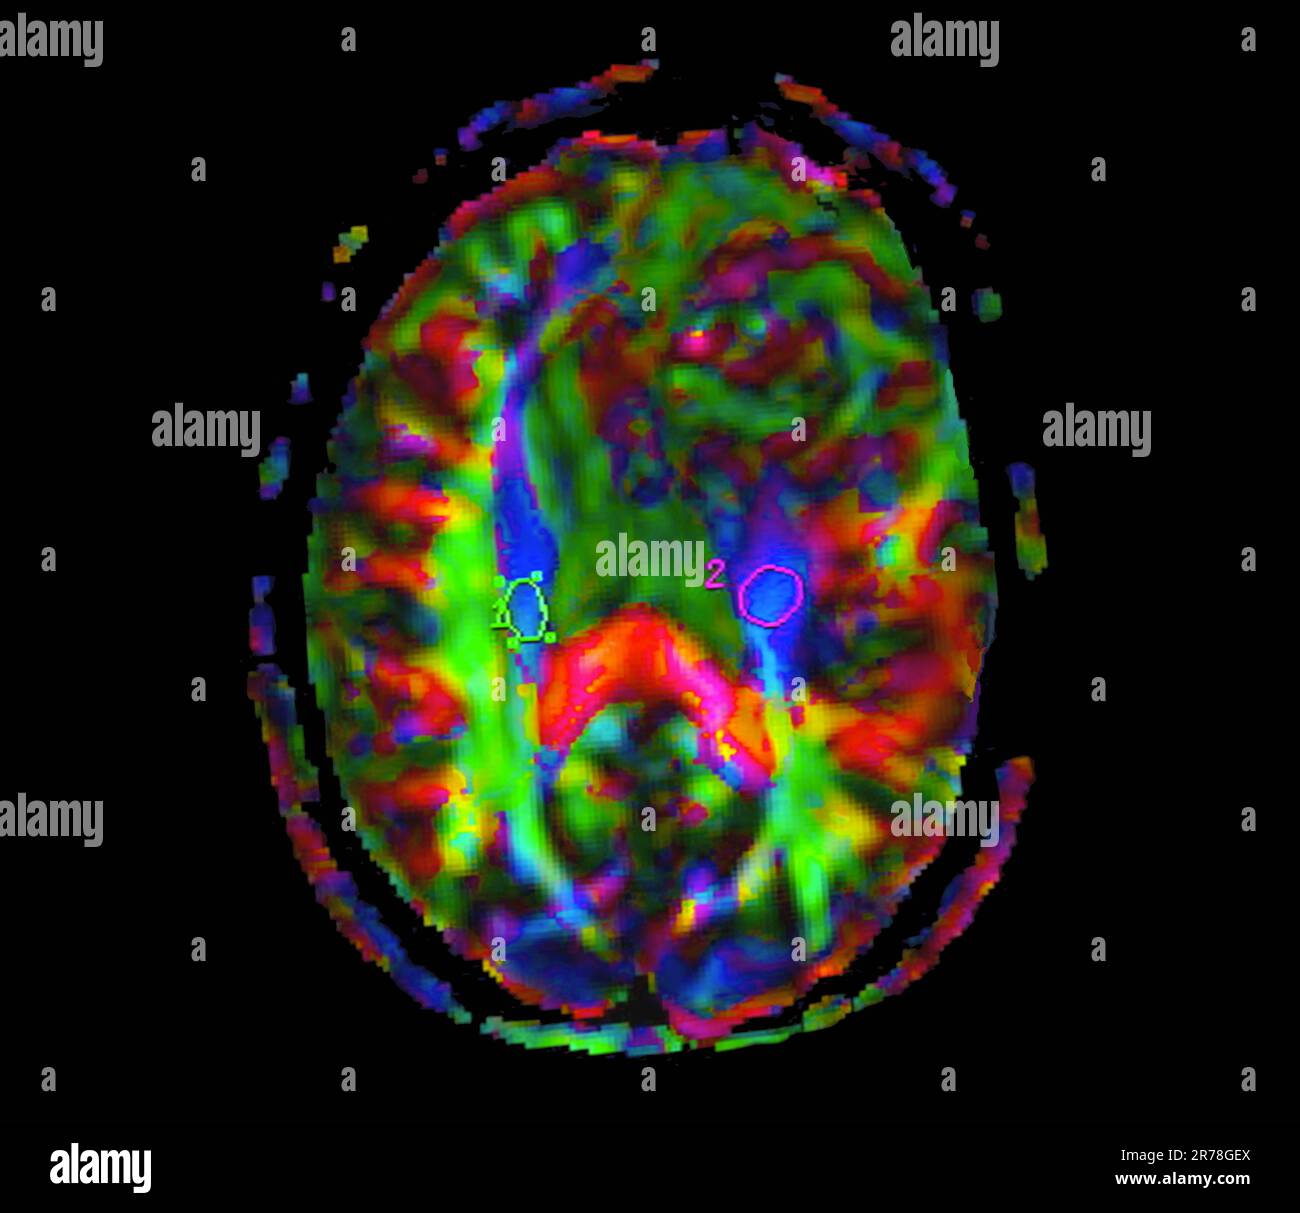

Was Ist Eine Läsion Im Gehirn. Abbildung 1ad T2Läsion Es gibt verschiedene Arten von Hirnläsionen, die anhand ihrer Symptome, körperlichen Untersuchungsbefunde und diagnostischen Tests unterschieden werden können. Auf keinen Fall sollten Kaltkompressen aus dem Gefrierschrank aufgelegt werden, weil dadurch das Hautgewebe durch Erfrierungen weiter geschädigt werden kann!

Eine Hirnläsion ist eine Art von Anomalie im Gehirn, die normalerweise durch eine Krankheit oder Verletzung verursacht wird Hirnläsionen: eine anatomische Abnormalität eines Teils des Gehirns Aber was sind Läsionen im Gehirn? Und was verursacht sie? Wie schwerwiegend sind Hirnläsionen und wie werden sie behandelt? Hier finden Sie Informationen zu diesem verwirrenden und beunruhigenden Gesundheitsproblem.